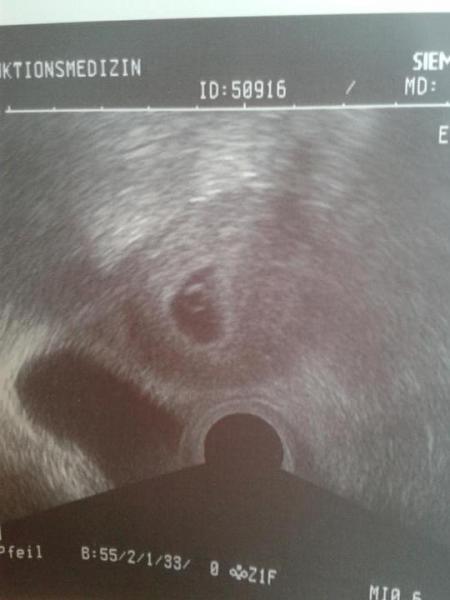

Achso ich habe ja das wichtigste vergessen: Bei meinem ersten US haben sich drei Fruchthüllen gezeig. In der mittleren war schon unser kleiner Murmel zu sehen und die anderen beiden sind noch Ü-Eier. Die überraschung erfahre ich am 8.1 und wir sind total aufgeregt. :-)

"Nur" eins ;-) das aber da wos hingehört und zeitgerecht entwickelt ;-)

Bild zu